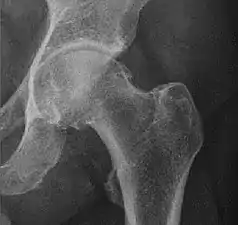

Landmarks

In the adult hip there are important landmarks to be recognized on plain film radiographs:[3]

- The iliopectineal or iliopubic line is formed by the arcuate line of the ilium and the superior border of the superior pubic ramus up to the pubic symphysis. It conforms to the inner margin of the pelvic ring and it is part of the anterior column of the acetabulum.

- The ilioischial line of Köhler begins at the medial border of the iliac wing and extends along the medial border of the ischium to end at the ischial tuberosity. It is part of the posterior column of the acetabulum.

- The acetabular floor.

- The teardrop represents a summation of shadows. Its medial aspect corresponds to the inner cortex of the pelvis and the lateral edge with the acetabular notch and the anteroinferior portion of the quadrilateral plate. It is not present at birth but gradually develops due to pressure of the femoral head.